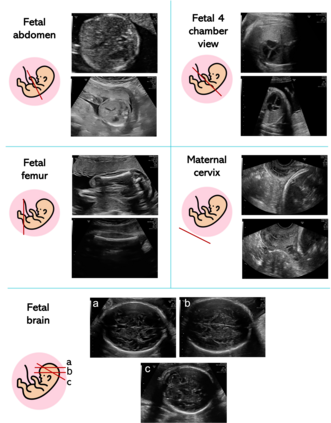

Deep-learning (DL) algorithms are becoming the standard for processing ultrasound (US) fetal images. Despite a large number of survey papers already present in this field, most of them are focusing on a broader area of medical-image analysis or not covering all fetal US DL applications. This paper surveys the most recent work in the field, with a total of 145 research papers published after 2017. Each paper is analyzed and commented on from both the methodology and application perspective. We categorized the papers in (i) fetal standard-plane detection, (ii) anatomical-structure analysis, and (iii) biometry parameter estimation. For each category, main limitations and open issues are presented. Summary tables are included to facilitate the comparison among the different approaches. Publicly-available datasets and performance metrics commonly used to assess algorithm performance are summarized, too. This paper ends with a critical summary of the current state of the art on DL algorithms for fetal US image analysis and a discussion on current challenges that have to be tackled by researchers working in the field to translate the research methodology into the actual clinical practice.